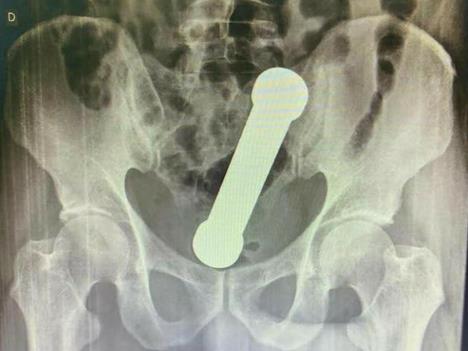

On se pojavio u bolnici u Manausu požalivši se na bolove u stomaku, mučninu i zatvor. Nakon rektalnog pregleda, lekari nisu mogli da pronađu uzrok njegovih problema pa su zatražili rendgenski snimak abdomena.

Rendgen je otkrio da je teg dugačak skoro 20 centimetara zaglavljen na mestu gde se debelo crevo spaja sa rektumom.